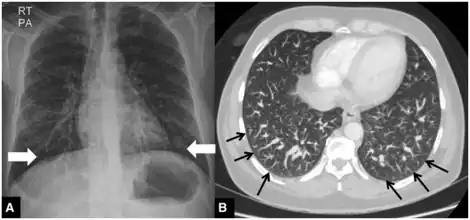

a) Hepatopulmonary syndrome type 1 b) dilated distal pulmonary arteries